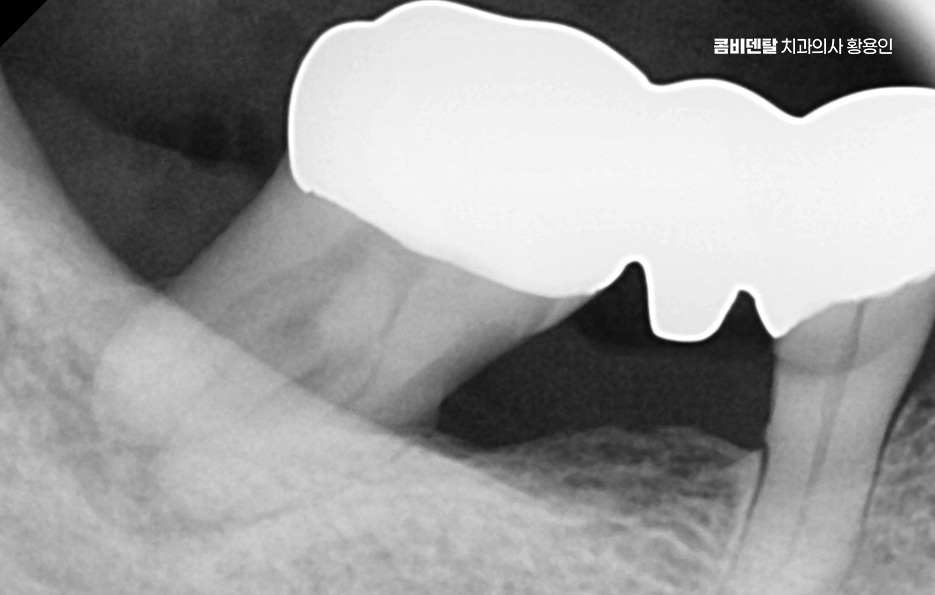

어금니 임플란트 치료 시 먼저 고려해야 할 주의사항은 뼈의 상태로 임플란트는 뼈에 직접 고정되는 구조이기 때문에, 뼈의 양과 질이 충분하지 않으면 안정적인 고정이 어렵고 특히 어금니 부위는 발치 후 뼈 흡수가 빠르게 진행되는 경향이 있어서, 오랜 기간 방치한 경우에는 임플란트를 바로 심기 어려운 상황이 될 수도 있었어요

어금니 임플란트 뼈이식 필요한 대표적 케이스는 어금니를 뽑은 지 오래된 경우로 치아가 빠진 뒤에는 그 자리를 채우던 뼈가 더 이상 필요 없다고 인식하고 점점 흡수되며 치주 질환으로 인해 어금니를 상실한 경우도 뼈이식이 필요한 경우가 많은데 치주 질환은 잇몸뿐 아니라 치아를 지지하는 뼈까지 함께 파괴하기 때문에, 발치 당시 이미 뼈가 상당히 소실된 상태인 경우가 많을 수 있었어요

상악 어금니의 경우에는 상악동이라는 구조도 고려해야 하며 위쪽 어금니 위에는 상악동이라는 빈 공간이 있는데 치아를 뽑고 시간이 지나면 이 공간이 아래로 내려오면서 임플란트를 심을 공간이 줄어들 수 있고 이런 경우에는 상악동 거상술이라는 수술과 함께 상악동 쪽 뼈를 보완하는 방식의 뼈이식이 필요해질 수 있었어요.

뼈이식이 필요하다고 해서 모두 같은 방식으로 진행되는 것은 아니며 부족한 뼈의 양과 위치에 따라 치료 방법과 범위는 달라지며 소량의 보완만 필요한 경우에는 임플란트를 심으면서 동시에 진행되기도 하고, 뼈 상태가 많이 부족한 경우에는 일정 기간 뼈가 자리 잡을 시간을 갖고 나서 임플란트를 진행하기도 해서 이 과정은 개인 상태에 따라 달라지기 때문에, 획일적으로 생각하기보다는 맞춤 계획으로 접근해야 하는 거예요